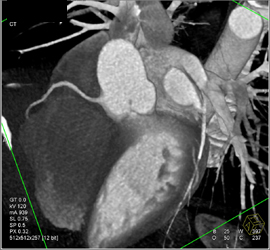

Normal Coronary Arteries